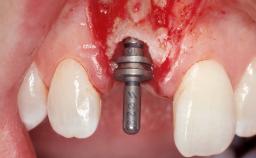

Immediate Flapless Placement of an Implant in a Maxillary Left Central Incisor Site

A 42-year-old female patient was referred to our clinic at the School of Dentistry of the University of São Paulo in November 2004, presenting a deficient restoration in the upper left central incisor. The clinical examination revealed no gingival retraction or any signs of gingival inflammation and, therefore, previous periodontal treatment was not considered. The patient presented a high lip line at full smile and a thin tissue biotype. This combination characterized a high-risk situation from an anatomic point of view, which required careful preoperative planning and cautious surgical execution.

Placement Protocol Immediate implant placement

Socket Morphology Single-root socket

Socket Integrity Sufficient, with intact bone walls